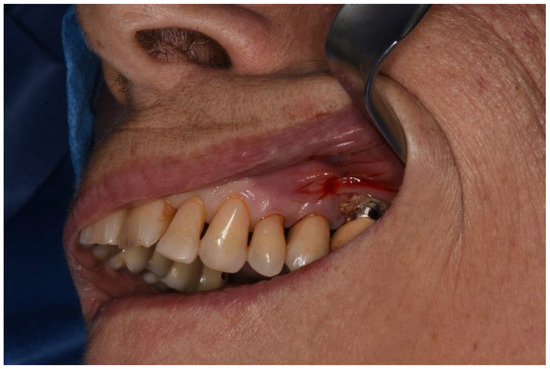

Figure 2. Clinical view.